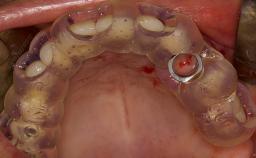

- Details of surgical techniques for SFE

- Recent advances regarding the SFE techniques